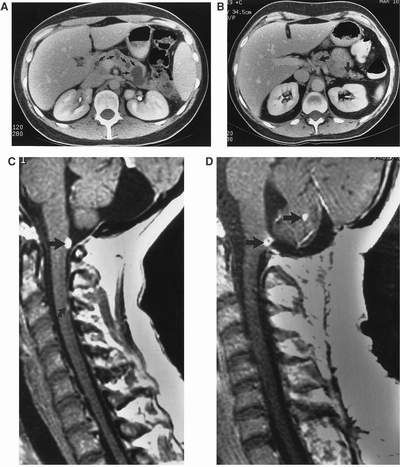

Hội chứng Von Hippel-Lindau (VHL) là một tình trạng di truyền liên quan đến các khối u xuất hiện trong nhiều cơ quan. Các khối u trong hội chứng này bao gồm u nguyên bào mạch máu (hemangioblastomas). Đây là các khối u mạch máu ở não, tủy sống và mắt.

Những người bị hội chứng Von Hippel-Lindau (VHL) cũng tăng nguy cơ phát triển ung thư tế bào thận, u tủy thượng thận và u thần kinh nội tiết tụy.

Các đặc điểm khác của hội chứng này bao gồm: u nang thận, nang tụy, u nang mào tinh hoàn và khối u túi cùng nội bạch huyết.

- Khối u nguyên bào mạch máu (lành tính) ở não và cột sống;

- U máu võng mạc;

- U tủy thượng thận trong hoặc ngoài tuyến thượng thận;

- Ung thư biểu mô tế bào thận (khối u ung thư thận).

Trong các trường hợp hiếm, một số người phát triển khối u túi cùng nội bạch huyết (khối u tai có thể gây điếc nếu không được phát hiện), khối u tụy và u nang mào tinh hoàn hoặc dây chằng rộng. Các biểu hiện khác bao gồm u nang (túi chất lỏng) thận và tuyến tụy.